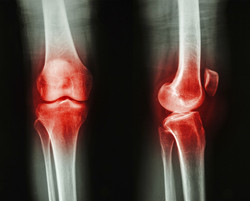

Le malattie infiammatorie croniche sono una causa prevalente di morbilità nell'UE e comportano costi rilevanti in termini di assistenza medica e perdita di ore di lavoro. L'infiammazione cronica è associata al rilascio massiccio di molecole di segnalazione specifiche, le citochine, e di enzimi, che alterano la risposta antimicrobica. In definitiva, questa situazione determina la riduzione della funzione degli organi e la distruzione dei tessuti, come avviene nella fibrosi cistica, nell'asma, nella broncopneumopatia ostruttiva cronica e nell'enfisema. I neutrofili sono leucociti dalla vita breve, che svolgono funzioni molto importanti per la difesa dell'organismo. Si tratta di globuli bianchi che vengono richiamati dal midollo osseo, tramite la circolazione, verso i tessuti interessati, in risposta ai segnali di pericolo. Questa risposta infiammatoria immediata e vitale può però ritorcersi contro l'organismo, se la sua intensità e la sua durata non sono più sotto controllo, finendo per danneggiare i tessuti. Il ruolo protettivo/patologico dei neutrofili è dimostrato dalle funzioni delle NSP (serina proteasi dei neutrofili), potenti enzimi dei granuli che idrolizzano le altre proteine. Queste proteasi uccidono direttamente i patogeni e ne disattivano le tossine, ma possono anche essere pericolose, poiché alimentano la risposta infiammatoria e distruggono le proteine della matrice extracellulare e delle difese immunitarie. I dati preliminari indicano che l'inibitore di proteasi serpinaB1 è necessario per preservare la riserva di neutrofili del midollo osseo e per proteggere le cellule epiteliali dei polmoni contro le NSP. La serpinaB1 è uno dei migliori inibitori delle tre NSP: elastasi neutrofila, catepsina G e proteinasi-3. Il progetto Marie Curie SERPINB1 ("Role of serpinB1 in cellular homeostasis in the bone marrow and the lung"), finanziato dall'UE, si propone di indagare sulla regolazione delle NSP da parte della serpinaB1 in condizioni di salute e di malattia. I ricercatori hanno scoperto che la serpinaB1 previene la morte dei neutrofili sia nei siti infiammatori sia nel midollo osseo e ne hanno studiato la funzione nello sviluppo dell'enfisema in età avanzata e in un modello di esposizione al fumo di sigaretta in ratti che ne erano carenti. I risultati mostrano che la serpinaB1 non è essenziale per la regolazione della portata del danno enfisematoso nei polmoni in seguito all'esposizione cronica al fumo. Tra i risultati del progetto vi è anche la scoperta che la catepsina G induce la morte delle cellule neutrofile e che la serpinaB1 è essenziale per bloccare tale percorso nei neutofili. SERPINB1 ha creato una piattaforma di conoscenze rilevante sui percorsi infiammatori implicati nelle malattie polmonari, che permetterà di sviluppare nuove terapie mirate a livello molecolare.